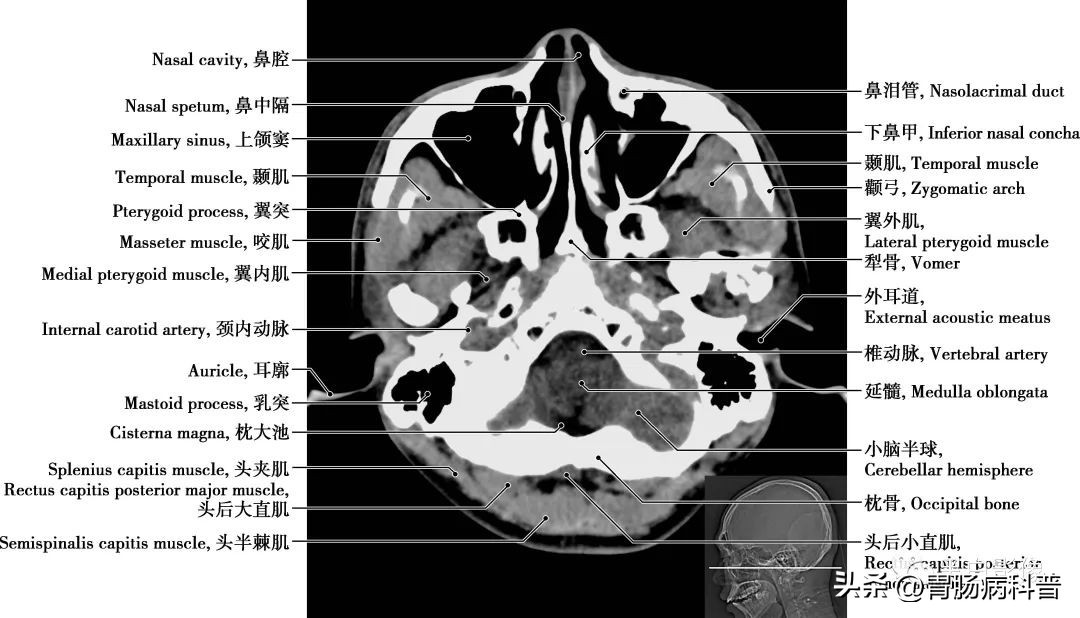

图1-1-19 经小脑扁桃体轴位切面

上颌窦 为上颌骨体内的锥形空腔,位于上颌骨体内,窦壁为骨质,覆黏膜,向内侧开口于中鼻道,分为一底、一尖及前、后、上、下四个壁。由于窦口高于窦底部,故在直立位时若有炎性物不易自然流出。外耳道 为外耳门至鼓膜的管道,呈弯曲状,由外向内,先向前上,继而稍向后,弯向前下

图1-1-20 经枕骨大孔轴位切面

小脑扁桃体 小脑下面靠小脑蚓两侧小脑半球的突起称小脑扁桃体。鼻中隔 把鼻腔分成左右两部分的组织,由骨、软骨和黏膜构成。鼻中隔骨结构由筛骨垂直板、犁骨和鼻中隔软骨共同构成,多偏向一侧。腮腺 最大的一对唾液腺,位于两侧面颊近耳垂处